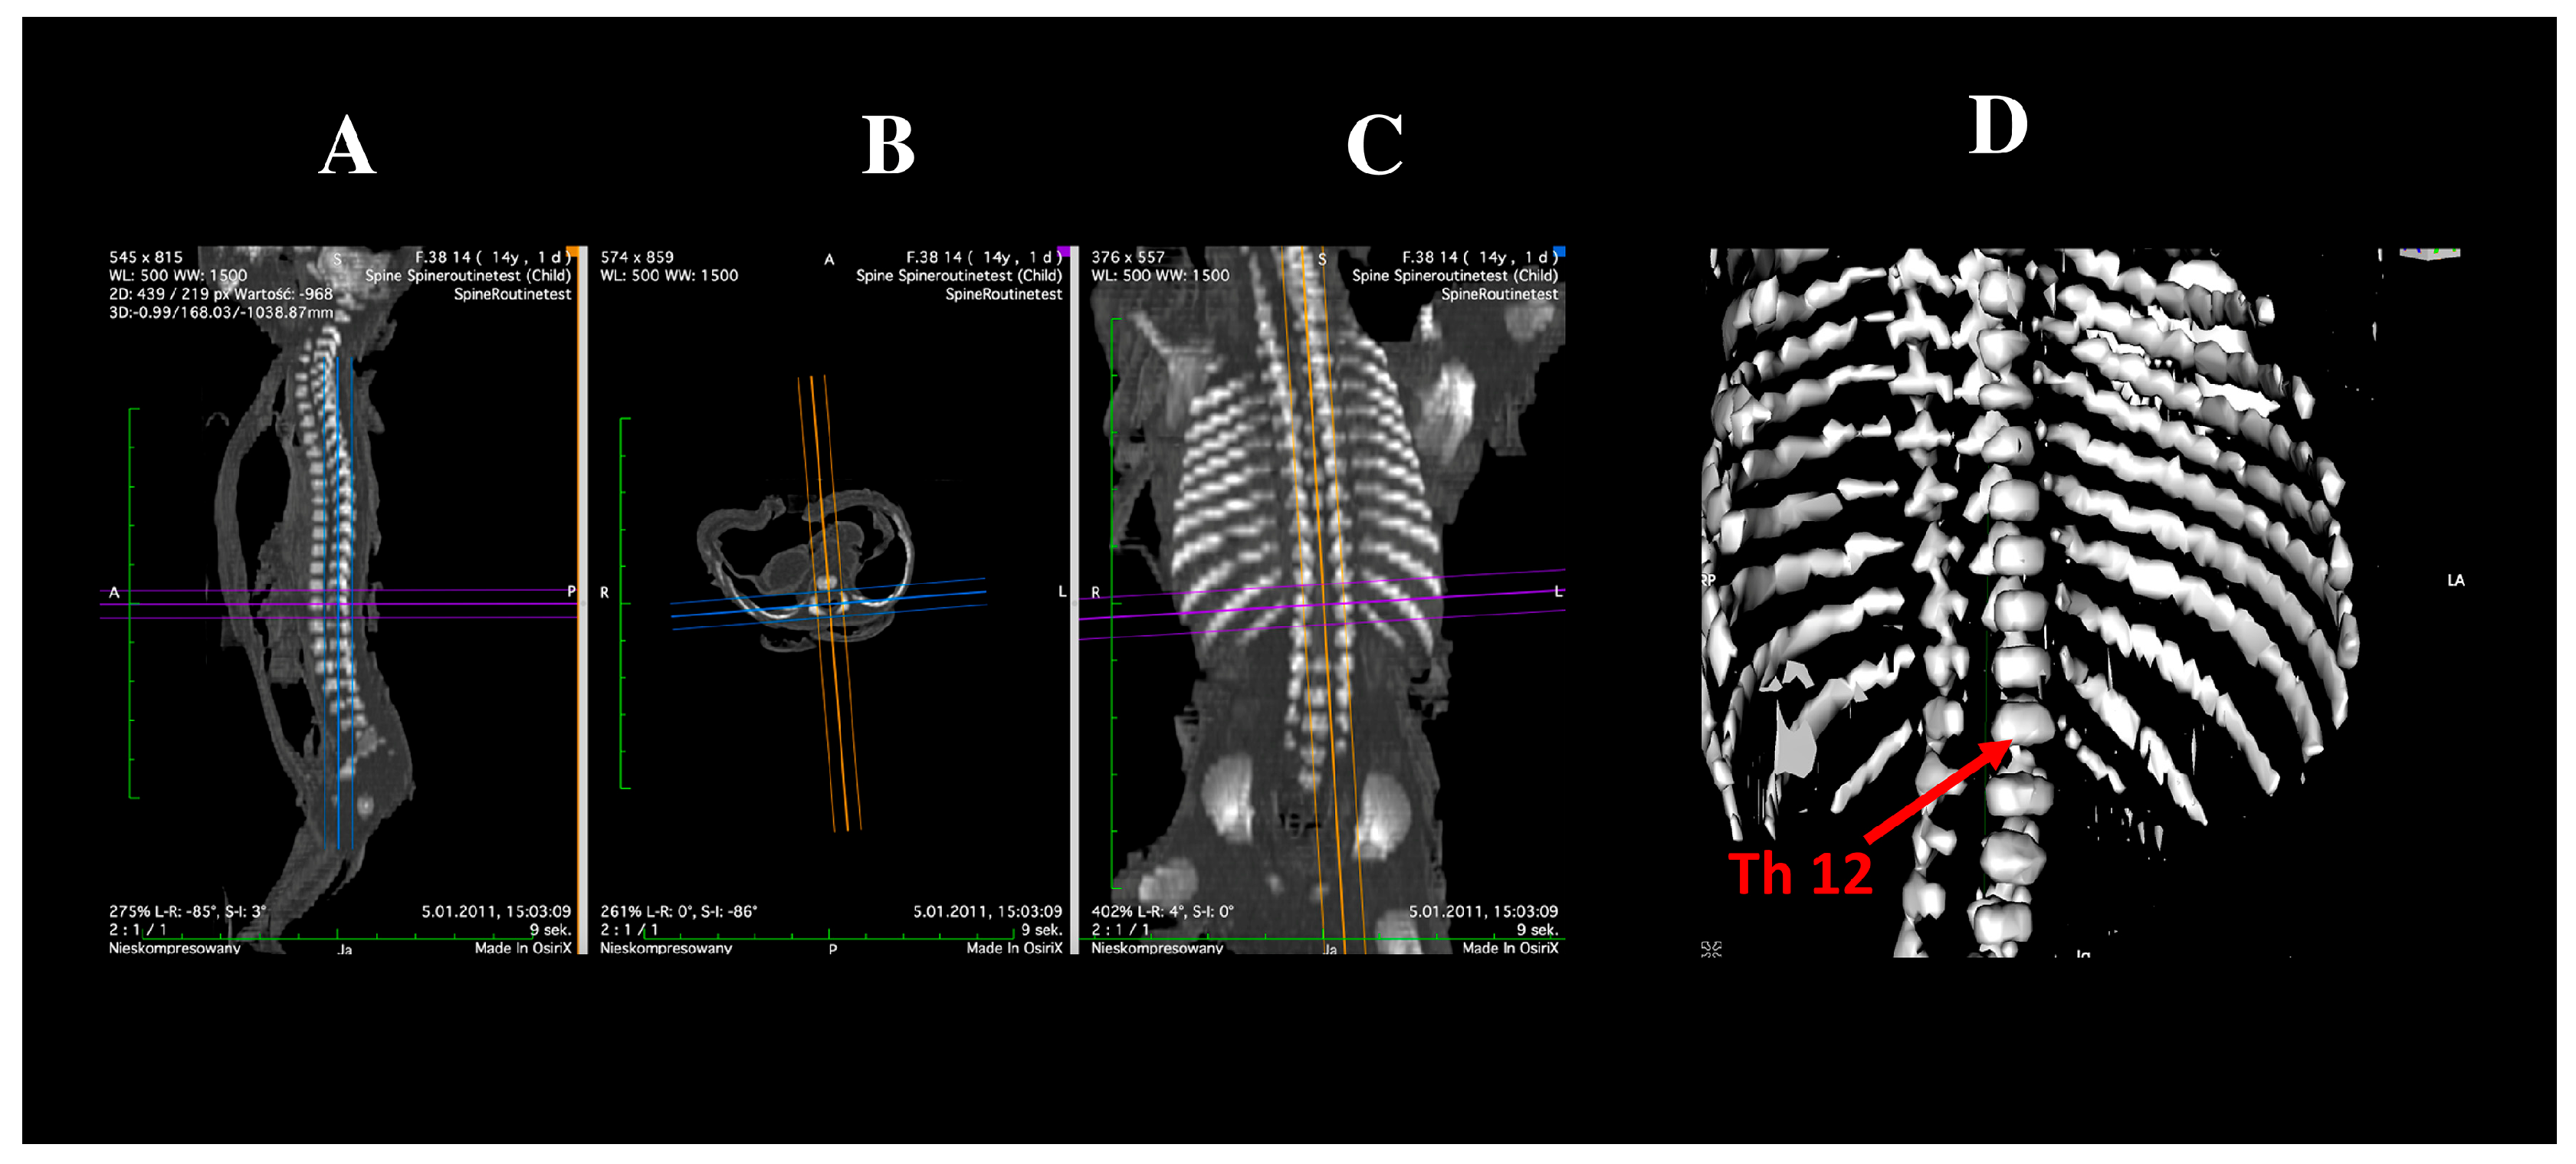

2.2. Morphometric Measurements and Assessment of Ossification Centers

- Transverse diameter of the vertebral body ossification center—defined as distance between the left and right borders of the center in the transverse plane (Figure 2);

- Sagittal diameter of the vertebral body ossification center—measured as the distance between the anterior and posterior borders of the center in the transverse plane (Figure 2);

- Cross-sectional area of the vertebral body ossification center—calculated by tracing its outline in the transverse plane (Figure 2);

- Length of the right and left neural process ossification centers—defined as distance between the proximal and distal borders of each center in the transverse plan (Figure 2);

- Width of the right and left neural process ossification centers—measured in the transverse plane (Figure 2);

- Cross-sectional area of the right and left neural process ossification centers—determined by tracing their outlines in the transverse plane (Figure 2);

- Volume of each ossification center—computed using advanced diagnostic imaging software that enables three-dimensional reconstruction based on spatial position and tissue X-ray attenuation (Figure 2).